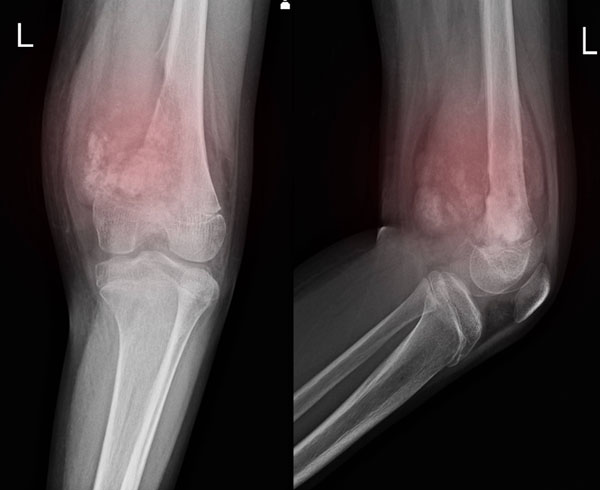

Limb salvage therapy based on comprehensive treatment is emphasized for bone and soft tissue malignant tumors. After extensive resection of local lesions, artificial prosthesis replacement, vascular reconstruction, allogeneic bone transplantation and other methods are adopted. Limb salvage treatment was performed for patients with malignant bone tumors of the limbs. Extensive resection was used for soft tissue sarcoma, especially for recurrent and refractory soft tissue sarcoma, and various free and pedicled skin flaps were used to repair postoperative soft tissue defects. Interventional vascular embolization and temporary vascular occlusion of abdominal aorta balloon were used to reduce intraoperative bleeding and remove the tumor safely for sacral and pelvic tumors. For metastatic tumors of bone, primary tumors of the spine and metastatic tumors, radiotherapy and chemotherapy were combined with surgery according to the conditions of the patients, and various internal fixation methods were used according to different sites.

Preoperative neoadjuvant chemotherapy is used for malignant tumors confirmed by pathology in order to eliminate micrometastasis, evaluate the effect of chemotherapeutic drugs, reduce the clinical stage of local tumors, and facilitate extensive surgical resection. It is clinically applied to some malignant bone tumors and soft tissue sarcomas.